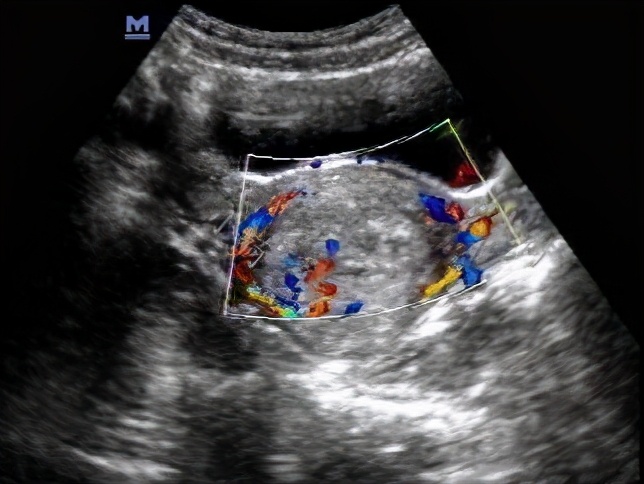

患者在入院后进行了相关检查,其中有血常规、电解质等生化项目,可见炎症指标均较高,同时给她还开立了子宫及双附件彩超,结果提示患者子宫内膜有不规则增厚,可见一鸡蛋大小的不规则肿物,且侵及肌层(图1)。

图1 子宫彩超显示子宫内膜不规则增厚,高度怀疑子宫内膜癌